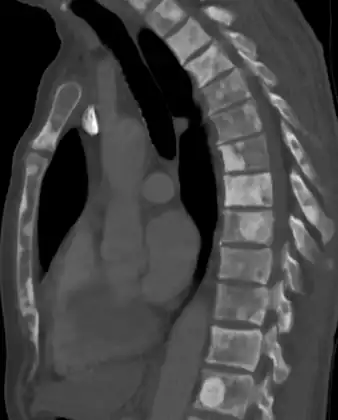

-

Sclerosis of the bones of the thoracic spine due to prostate cancer metastases (CT image) -

The most important distinction made by any staging system is whether the cancer is confined to the prostate. In the TNM system, clinical T1 and T2 cancers are found only in the prostate, while T3 and T4 cancers have metastasized. Several tests can be used to look for evidence of spread. Medical specialty professional organizations recommend against the use of PET scans, CT scans, or bone scans when a physician stages early prostate cancer with low risk for metastasis.[95] Those tests would be appropriate in cases such as when a CT scan evaluates spread within the pelvis, a bone scan looks for spread to the bones, and endorectal coil magnetic resonance imaging evaluates the prostatic capsule and the seminal vesicles. Bone scans should reveal osteoblastic appearance due to increased bone density in the areas of bone metastasis—the reverse of what is found in many other metastatic cancers.